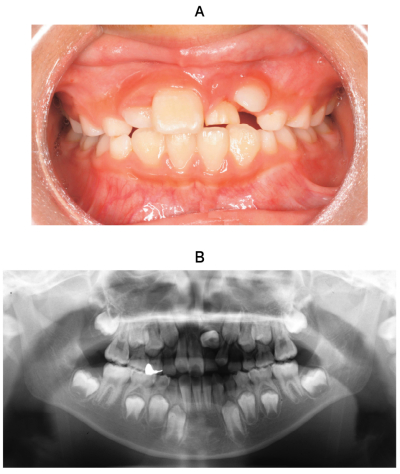

9歳の男児。上顎左側中切歯が生えてこないことを主訴として来院した。初診時の口腔内写真、エックス線画像及び歯科用コーンビーム CT 矢状断像を別に示す。

今後、⎿1において起こり得る異常はどれか。1つ選べ。